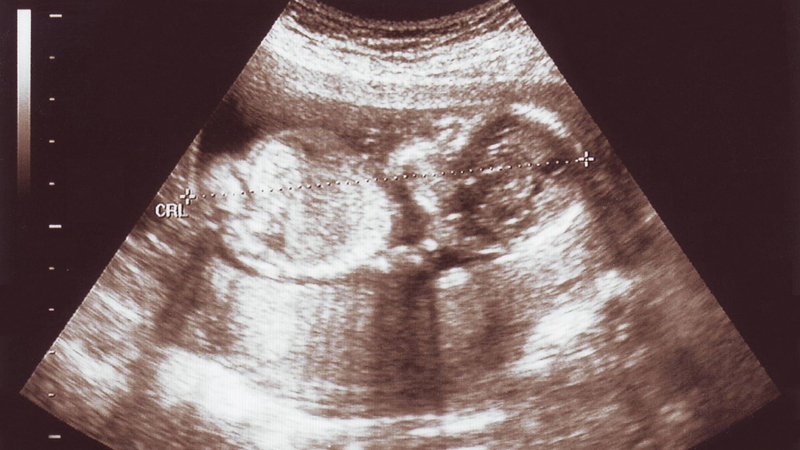

Thai 16 tuần nặng bao nhiêu gam là câu hỏi thắc mắc của nhiều mẹ

Ở tuần thai thứ 16 (tính từ kỳ kinh cuối, tương đương khoảng 14 tuần sau thụ tinh), thai nhi có nhiều bước tiến rõ rệt về vận động và cấu trúc cơ thể. Các nhóm cơ vùng lưng và dọc cột sống phát triển mạnh hơn, giúp đầu và cổ bé giữ thẳng và linh hoạt hơn trước. Nhãn cầu đã có thể di chuyển nhẹ bên trong hốc mắt, trong khi tai tiếp tục hoàn thiện, những xương nhỏ trong tai dần đảm nhận chức năng dẫn truyền rung động, tạo nền tảng cho khả năng cảm nhận âm thanh từ môi trường bên ngoài.

Tay và chân của thai nhi cũng phối hợp cử động nhịp nhàng hơn, các động tác co duỗi có thể quan sát được qua siêu âm. Dù vậy, các chuyển động này vẫn còn rất nhẹ nên phần lớn mẹ bầu chưa cảm nhận rõ thai máy ở thời điểm này. Song song với sự phát triển của em bé, cơ thể mẹ cũng thay đổi đáng kể, trong đó vòng ngực thường tăng kích thước do tuyến vú tiếp tục phát triển để chuẩn bị cho quá trình tiết sữa sau sinh.